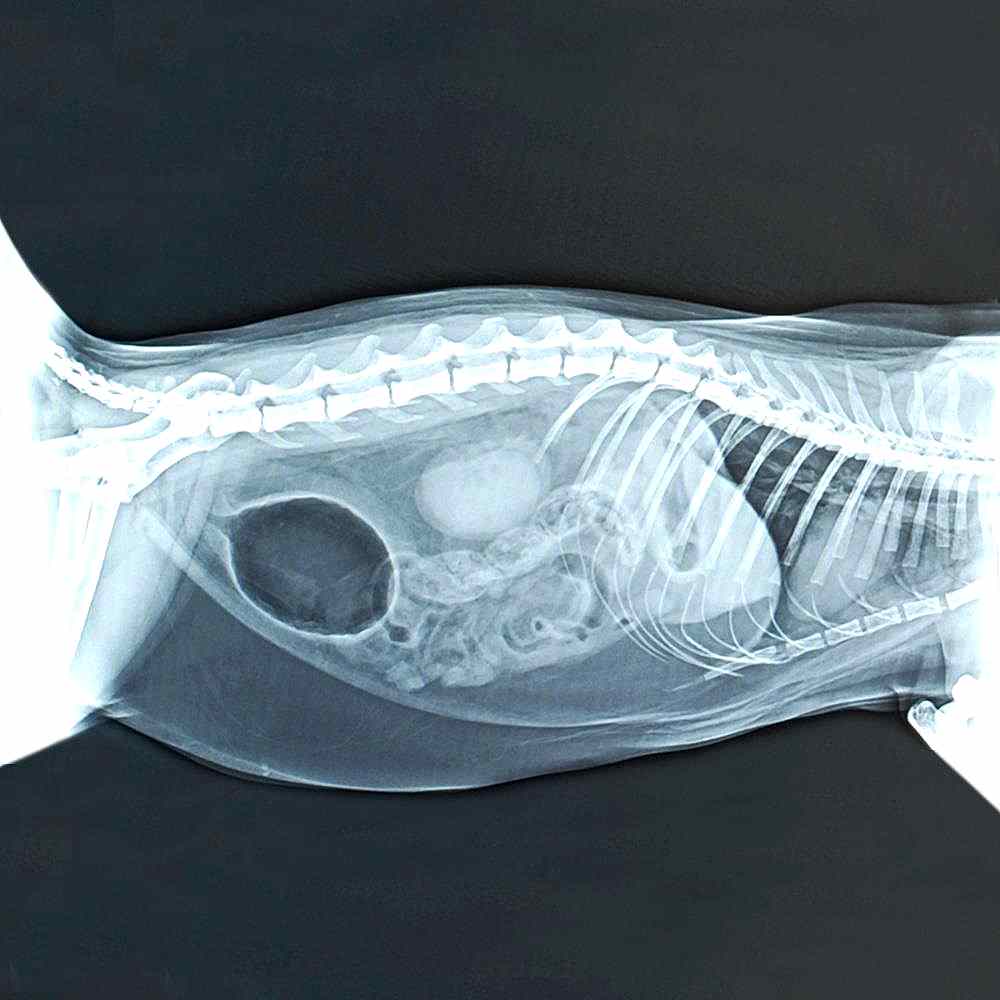

Kliniğimizde, bilgisayarlı röntgen (CR) cihazımızla direk ve radyopak maddeli grafiler alınmaktadır. Ayrıca kliniğimiz bünyesinde, penn hip yöntemi ile kalça displazilerinin erken teşhisleri yapılabilmektedir.